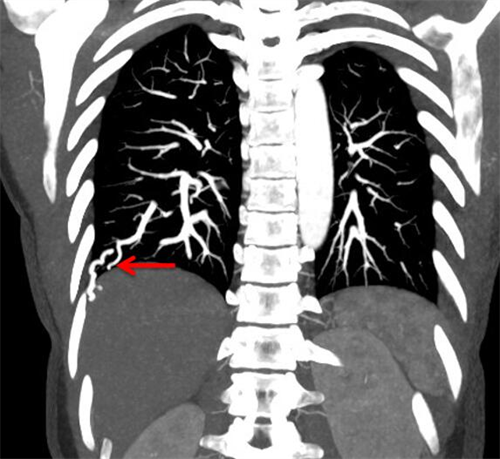

在经食道心脏超声下,检查提示心外右向左分流。行肺动脉CTA检查,提示右下肺前、外基底段动静脉瘘畸形改变。经过一步步抽丝剥茧,最终找到了导致梁瑶脑梗的真正原因——肺动静脉瘘。

红色箭头处为肺动静脉瘘位置